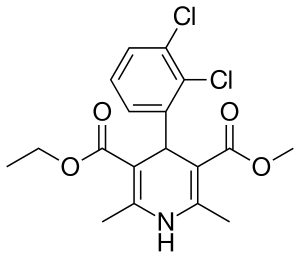

| Formula | C18H19Cl2NO4 |

| Molar mass | 384.25 g·mol−1 |

Felodipine is a member of the 1,4-dihydropyridine class of calcium channel blockers.[11]: 20–21 It is a racemic mixture, and is insoluble in water but is soluble in dichloromethane and ethanol.[11]: 25